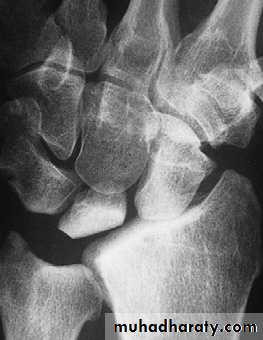

KIENBOCK’S DISEASE

a form of ischaemic necrosis, probably due to chronic stress or injury

Pathology:the pathological changes proceed in four stages

Clinical features:

Imaging:

Radioscintigraphy may reveal

increased activity

X-rays

MRI